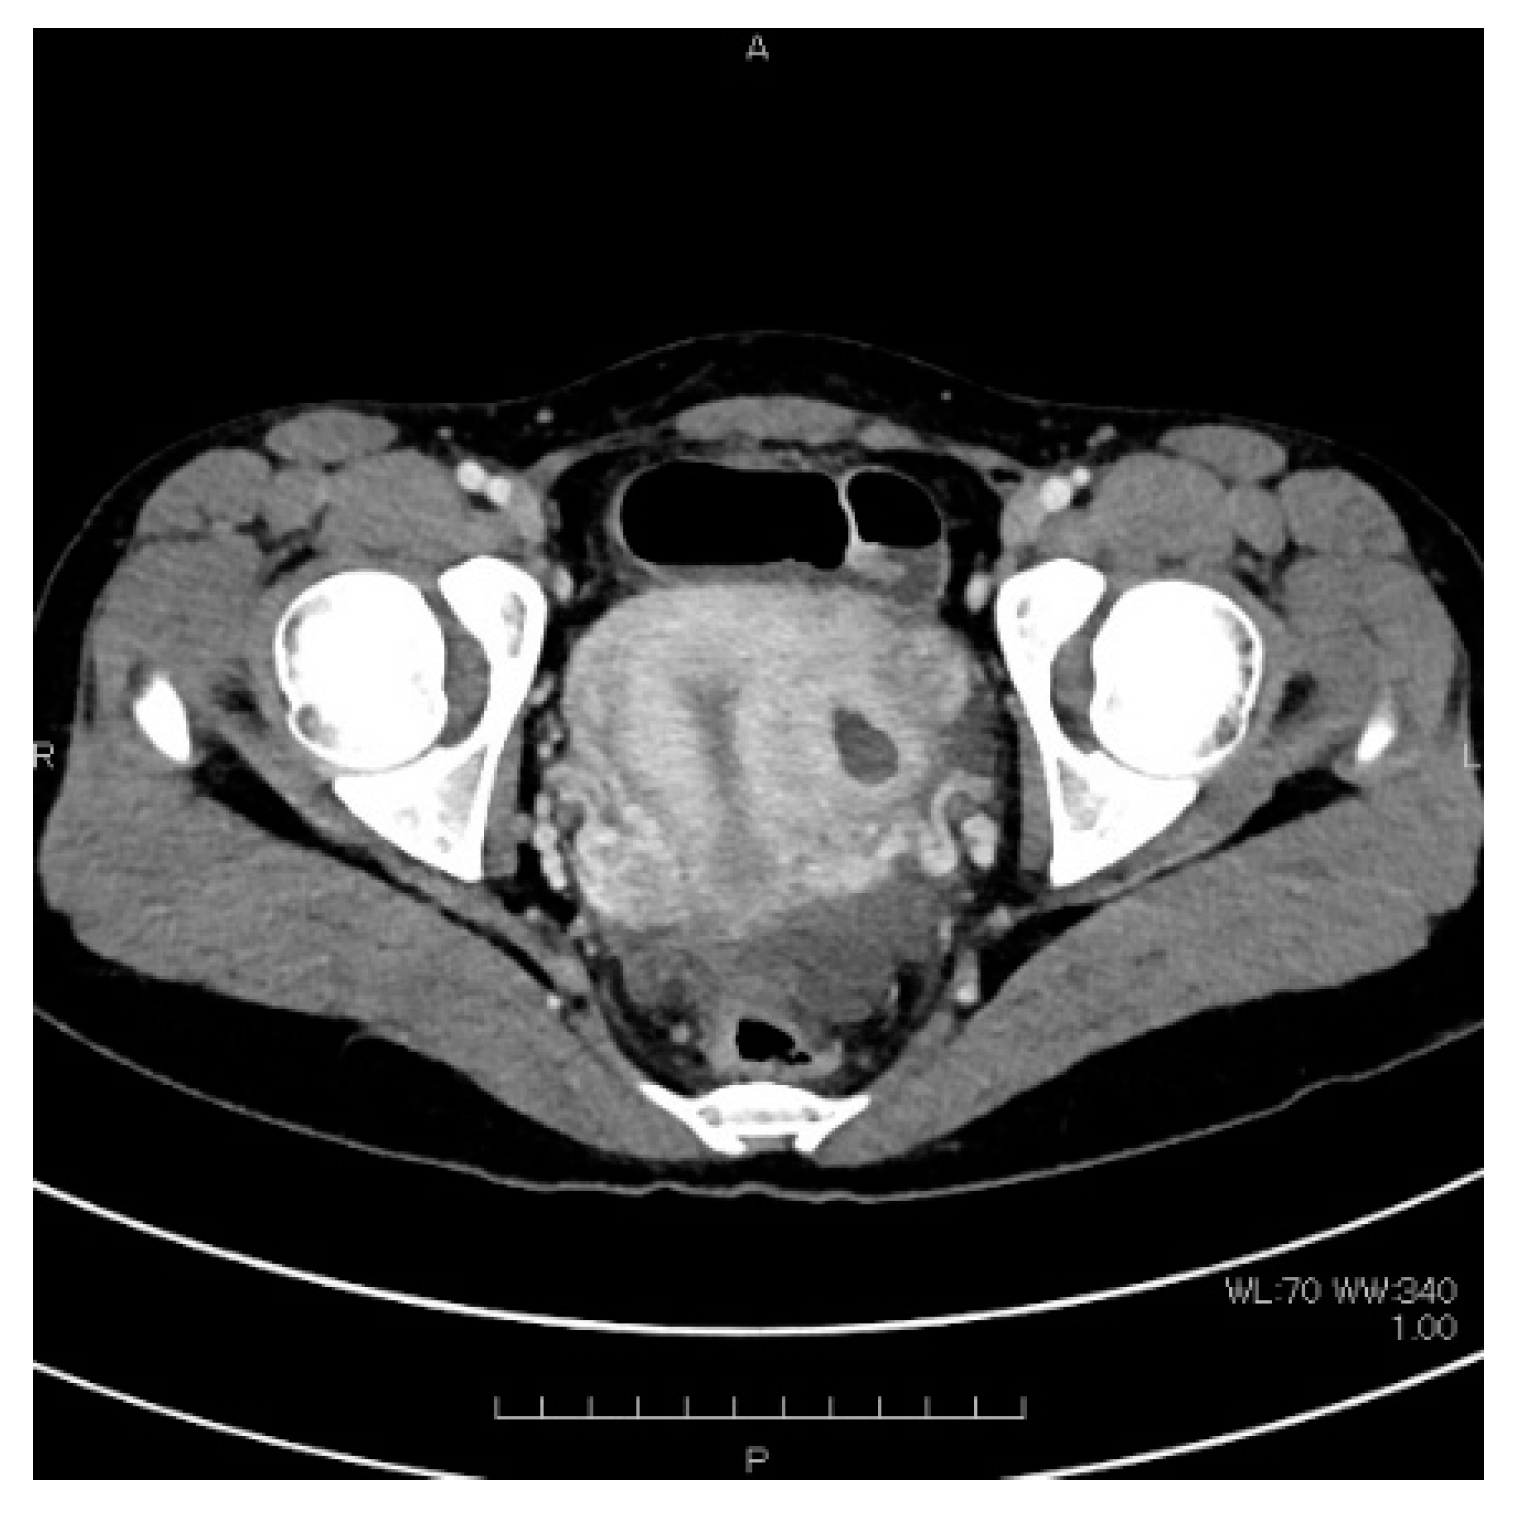

2. Case Presentation

| This case | 22 | 0 | 0 | 15 | 36 | L | 51.9 | None | CT, MRI: None | Laparoscopy | 3 cm, lateral, left side | Harmonic Scalpel, scissors forceps | 2 layers using 0 PDS | 14 | 69 | few | 2 | Present study |